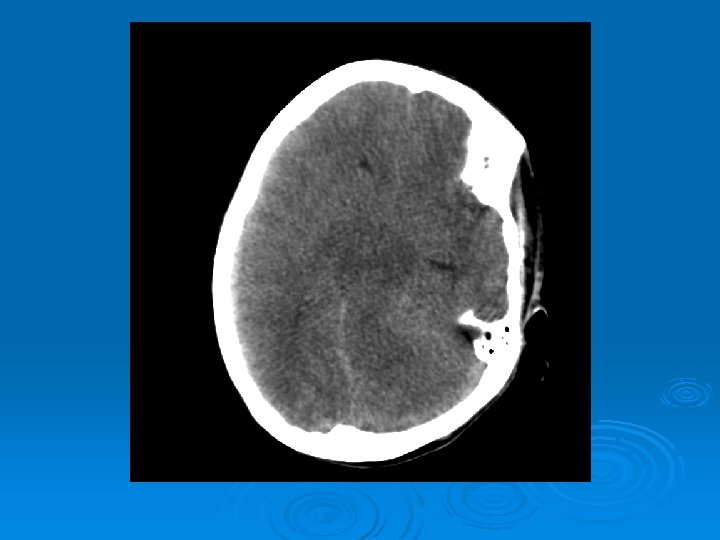

Course: Ø 3 PM, RN noticed anisocoria and L pupil non-reactive. Ø Neurology STAT dose mannitol and w/ dilantin. Ø Pt went for stat head Ct:

CT head 2/11/07 Ø A right frontal ventriculostomy catheter Ø Diffuse sulcal effacement with thickening of the cortex. Ø Loss of gray-white differentiation and hypodensity in the left parietooccipital region. Ø There is diffuse hypodensity of the cerebellum and brainstem. Ø Ø Ø The basilar cisterns are nearly completely effaced. Ø Impression: Ø Worsened diffuse cerebral edema The lateral ventricles are smaller

Course: Ø Neurosurgery saw pt: on exam she had lost cough, gag reflexes, corneal reflexes, she had flexed RUE, semipurposeful with bilateral extended LE. Ø Concern for herniation: placed Ø ICP 35 -40 10 th-11 th EVD